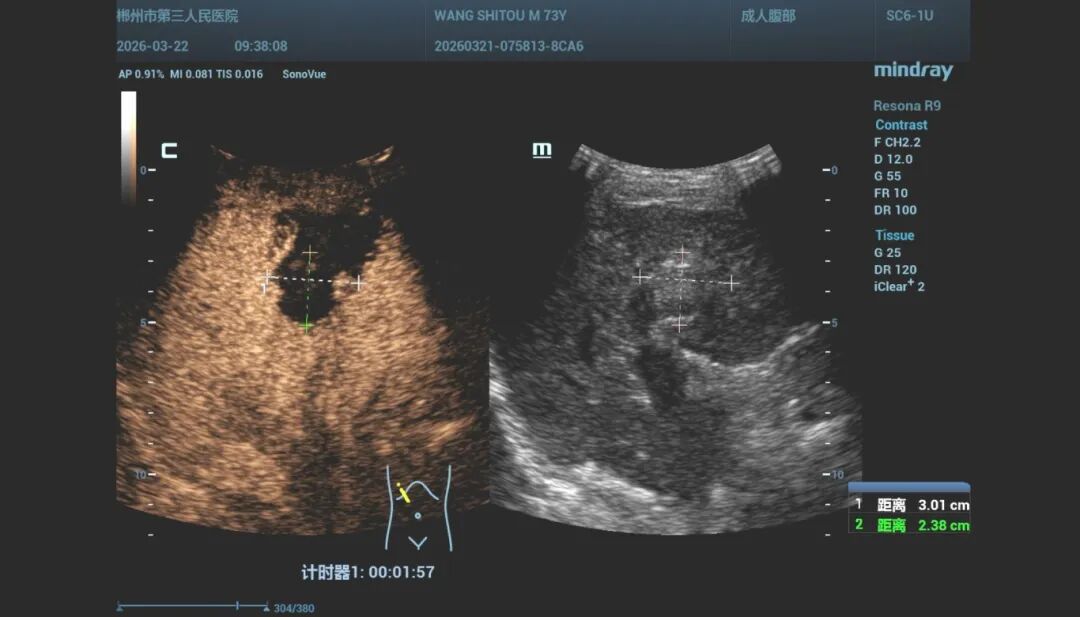

手术当天,我院超声中心、麻醉科手术室、肝胆外科团队与谢晓华教授紧密配合,凭借丰富的临床经验和精湛的技术,对患者病情进行全面评估,并精确规划穿刺路径。在超声的实时监控下,消融针精准命中肿瘤病灶,整个手术过程顺利,术后评估显示消融范围完全覆盖肿瘤,达到根治性治疗效果。

↑术后造影图